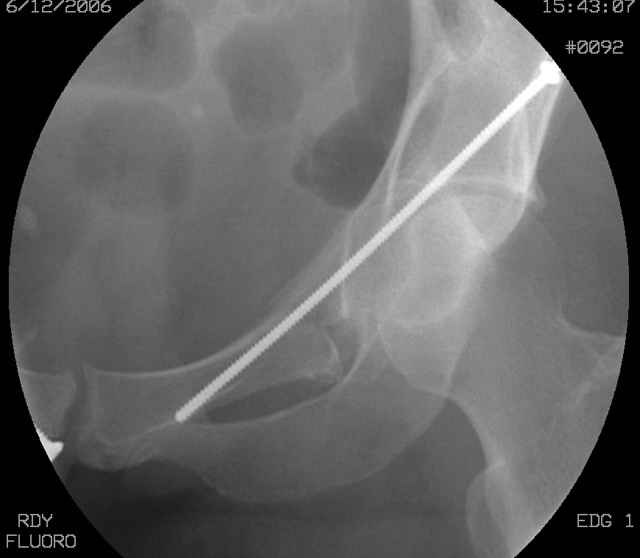

Understand that this is no simple fracture but in the same breath is very common and can be very routinely-simplistically treated without a variety of complicated and variable scenarios...keep it simple...turn him prone, clean him up, do a nice exposure, protect the nerve, remove the debris, save it and sort it out if you can, clean the fracture lines, manipulate and clamp the transverse, hold it how you choose (I'd recommend a percutaneously inserted 3.5mm antegrade medullary lag screw), remove the clamp, reduce the

small or impacted fragments to the head, reduce the wall, and support the wall and transverse with a balanced 3.5mm contoured reconstruction plate.

I'll include a few images of a similar injury in a similarly large male patient. This patient "showed up" in our ER c/o hip pain 2 months after being treated in the lateral position, without a quality reduction, without an anterior column transverse supporting implant, with an unbalanced plate applied too medially, with insufficient caudal segment fixation...it took over 8 hours and a 3+ l blood loss to debride the callus from front then

The 2nd example is of a motorcyclist with a transverse fracture-dislocation...he had a closed attempted reduction and placed in traction but the manipulative reduction was not concentric (not unusual for this injury pattern)...so the traction was adjusted to be just enough to disengage the head from the fracture (12#) until he could be cleared for surgery one day after injury...he was treated "urgently" then with a prone KL, clean the fracture, reduce and clamp it, screw it, support with a balanced plate, close, and enjoy...2-3hours, 400cc EBL, blah, blah, blah..

You can adjust the quadrilateral surface contact point as needed to get the fracture to reduce...we plan this based on the fracture orientation on the preop CT scan images...the clamp should be balanced to avoid over compressing one portion and distracting the other limb. Go back to and you¹ll see on the injury CT where the clamp tines need to be.

Here's a pic from the foot of the bed and you can see the clamp in the wound and the knee is extended so he must've had a tight rectus. The C-arm is rolled back to an obturator oblique image to reveal the anterior column...we put a slight outlet tilt to combine the images and give a better view of the anterior column...we can see the posterior column limb reduction in the wound, we can palpate the quadrilateral surface limb, and the image demonstrates the anterior column portion...you can adjust the tilt and rotation to image tangentially to the fracture plane if you'd like. We've inserted a 2mm K wire to site the starting point and aim/orientation for the drill and screw

Prone Imaging

OK, now we're inserting the drill percutaneosuy using a sleeve. This fluoro shot is not for this patient (notice no clamp) but I was too lazy to go searching the PACS for one with the clamp on, so pretend...I'll save the next ones and send along...the imaging is the same and the clamp doesn't obstruct imaging other than very rarely...you can always tilt the C-arm a bit to clear it if the clamp obstructs the exact spot that you'd like to see. We'll assume that everyone knows the safe zone for a medullary ramus screw. Use a calibrated drill and sleeve of known length to simplify your life...or use Alex's fancy cannulated screws...I like 3.5mm screws because the oscillating 2.5mm drill bounces and remains intraosseus when it oscillates and contacts endosteal cortical ramus... so will the screw, and like a long bent screw IF the fracture is clamped... if unclamped, when the screw contacts the endosteum, it pushes the reduction apart instead of bouncing. The big 7mm cannulated screws fit few patients and extrude...we very rarely use them any more...you'll see an old one later.

Prone Obturator-Outlet

Screw insertion using the obturator-outlet combination image.